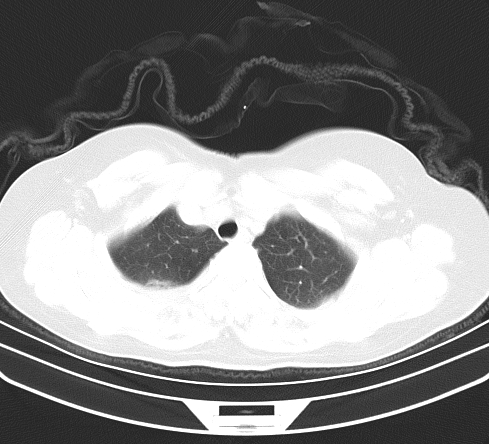

以下是引用余辉在2009-2-19 20:10:00的发言:[br]多考虑急性感染性病变,右中叶尚可见多枚小斑片状影,多为化脓性肺炎,双侧胸腔积液

以下是引用随光逐影在2009-2-19 20:33:00的发言:[br]1)考虑右肺炎症;建议抗炎治疗后复查。2)双侧胸腔积液(以右侧为甚)。

以下是引用花凤凰在2009-2-19 20:46:00的发言:[br]病人有发热,胸痛急性起病,主要病变位于右肺中叶外侧段,呈楔行改变,位于外带胸膜下,考虑为肺梗塞可能!!!!!!!!!!!!!!!!!!!!!!!!!!!!!!!!!!!